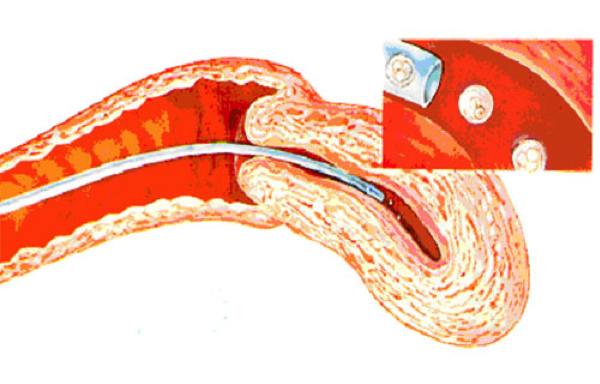

STEP 6 - EMBRYO REPLACEMENT

The embryos are transferred back into your womb. This method is usually pain free and you do not need any sedation. Your will need to discuss with your doctor on the number of embryos to be put into your womb. The more the number of embryos you put in, the higher is the risk of multiple pregnancies. Your doctor will usually limit to only 3 embryos and would advised you to freeze the surplus embryos if the qualities are good.

Following embryo replacement you will need to continue with some hormonal medications for further 14 days before you check your pregnancy test.